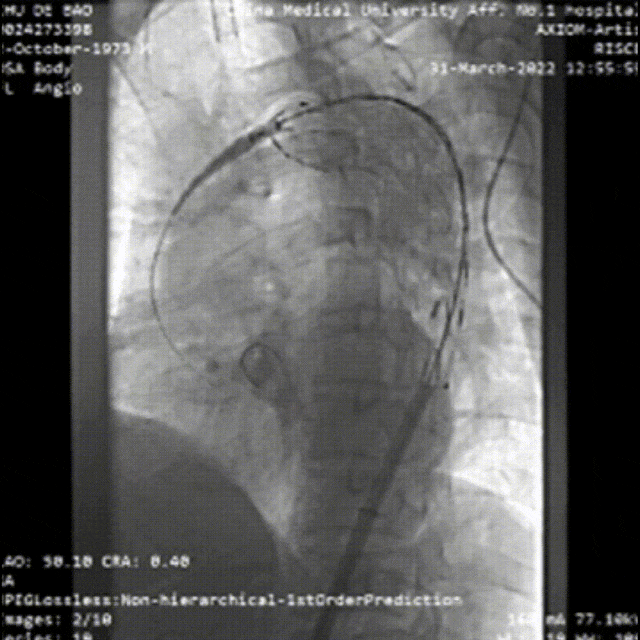

★病例4

急性复杂性AD

夹层累及股动脉(支架入路),需要参考术前CT,在彩超引导下穿刺入真腔,或者行股动脉剖开,直视下辨认真假腔。

术后处理:TEVAR后仍需关注脏器缺血等问题,必要时对分支血管进行进一步处理。